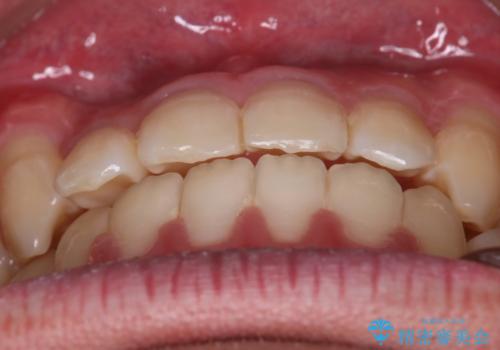

左右の噛み合わせが反対咬合であることと下顎の皮質骨が薄いため治療計画をしっかりと立てて行う必要のあるケースでした。

心配していた歯肉退縮も起こらず、前歯の噛み合わせと歯並びが綺麗に改善されました。

期間も1年2ヶ月と短期間で終了することができ、とても満足度の高い治療になりました。